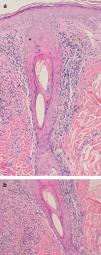

The condition is characterized by perifollicular keratotic papules and spinous follicular hyperkeratosis. The plaques progress to scarring alopecia (Fig. 2), which is generally multifocal caused by several simultaneous lesions. Patients usually report itching, burning, or pain on the scalp. Follicular openings with single hairs are seen in the center of some plaques while follicles containing groups of 2 or 3 hairs (tufted folliculitis) are observed in others. The skin on the plaques becomes parchment-like. The edges of the plaques are poorly defined and the skin in the center is smooth with no scaling. Hair loss is irreversible.

Examination of a biopsy specimen reveals a predominantly perifollicular lymphocytic infiltrate (Fig. 3) in the reticular dermis. In the mid-dermis a mucinous perifollicular fibroplasia is observed but no noticeable interfollicular mucin. Superficial perifollicular wedge-shaped scarring is also observed. Also characteristic is the absence of sebaceous glands and the arrector pili muscle.26